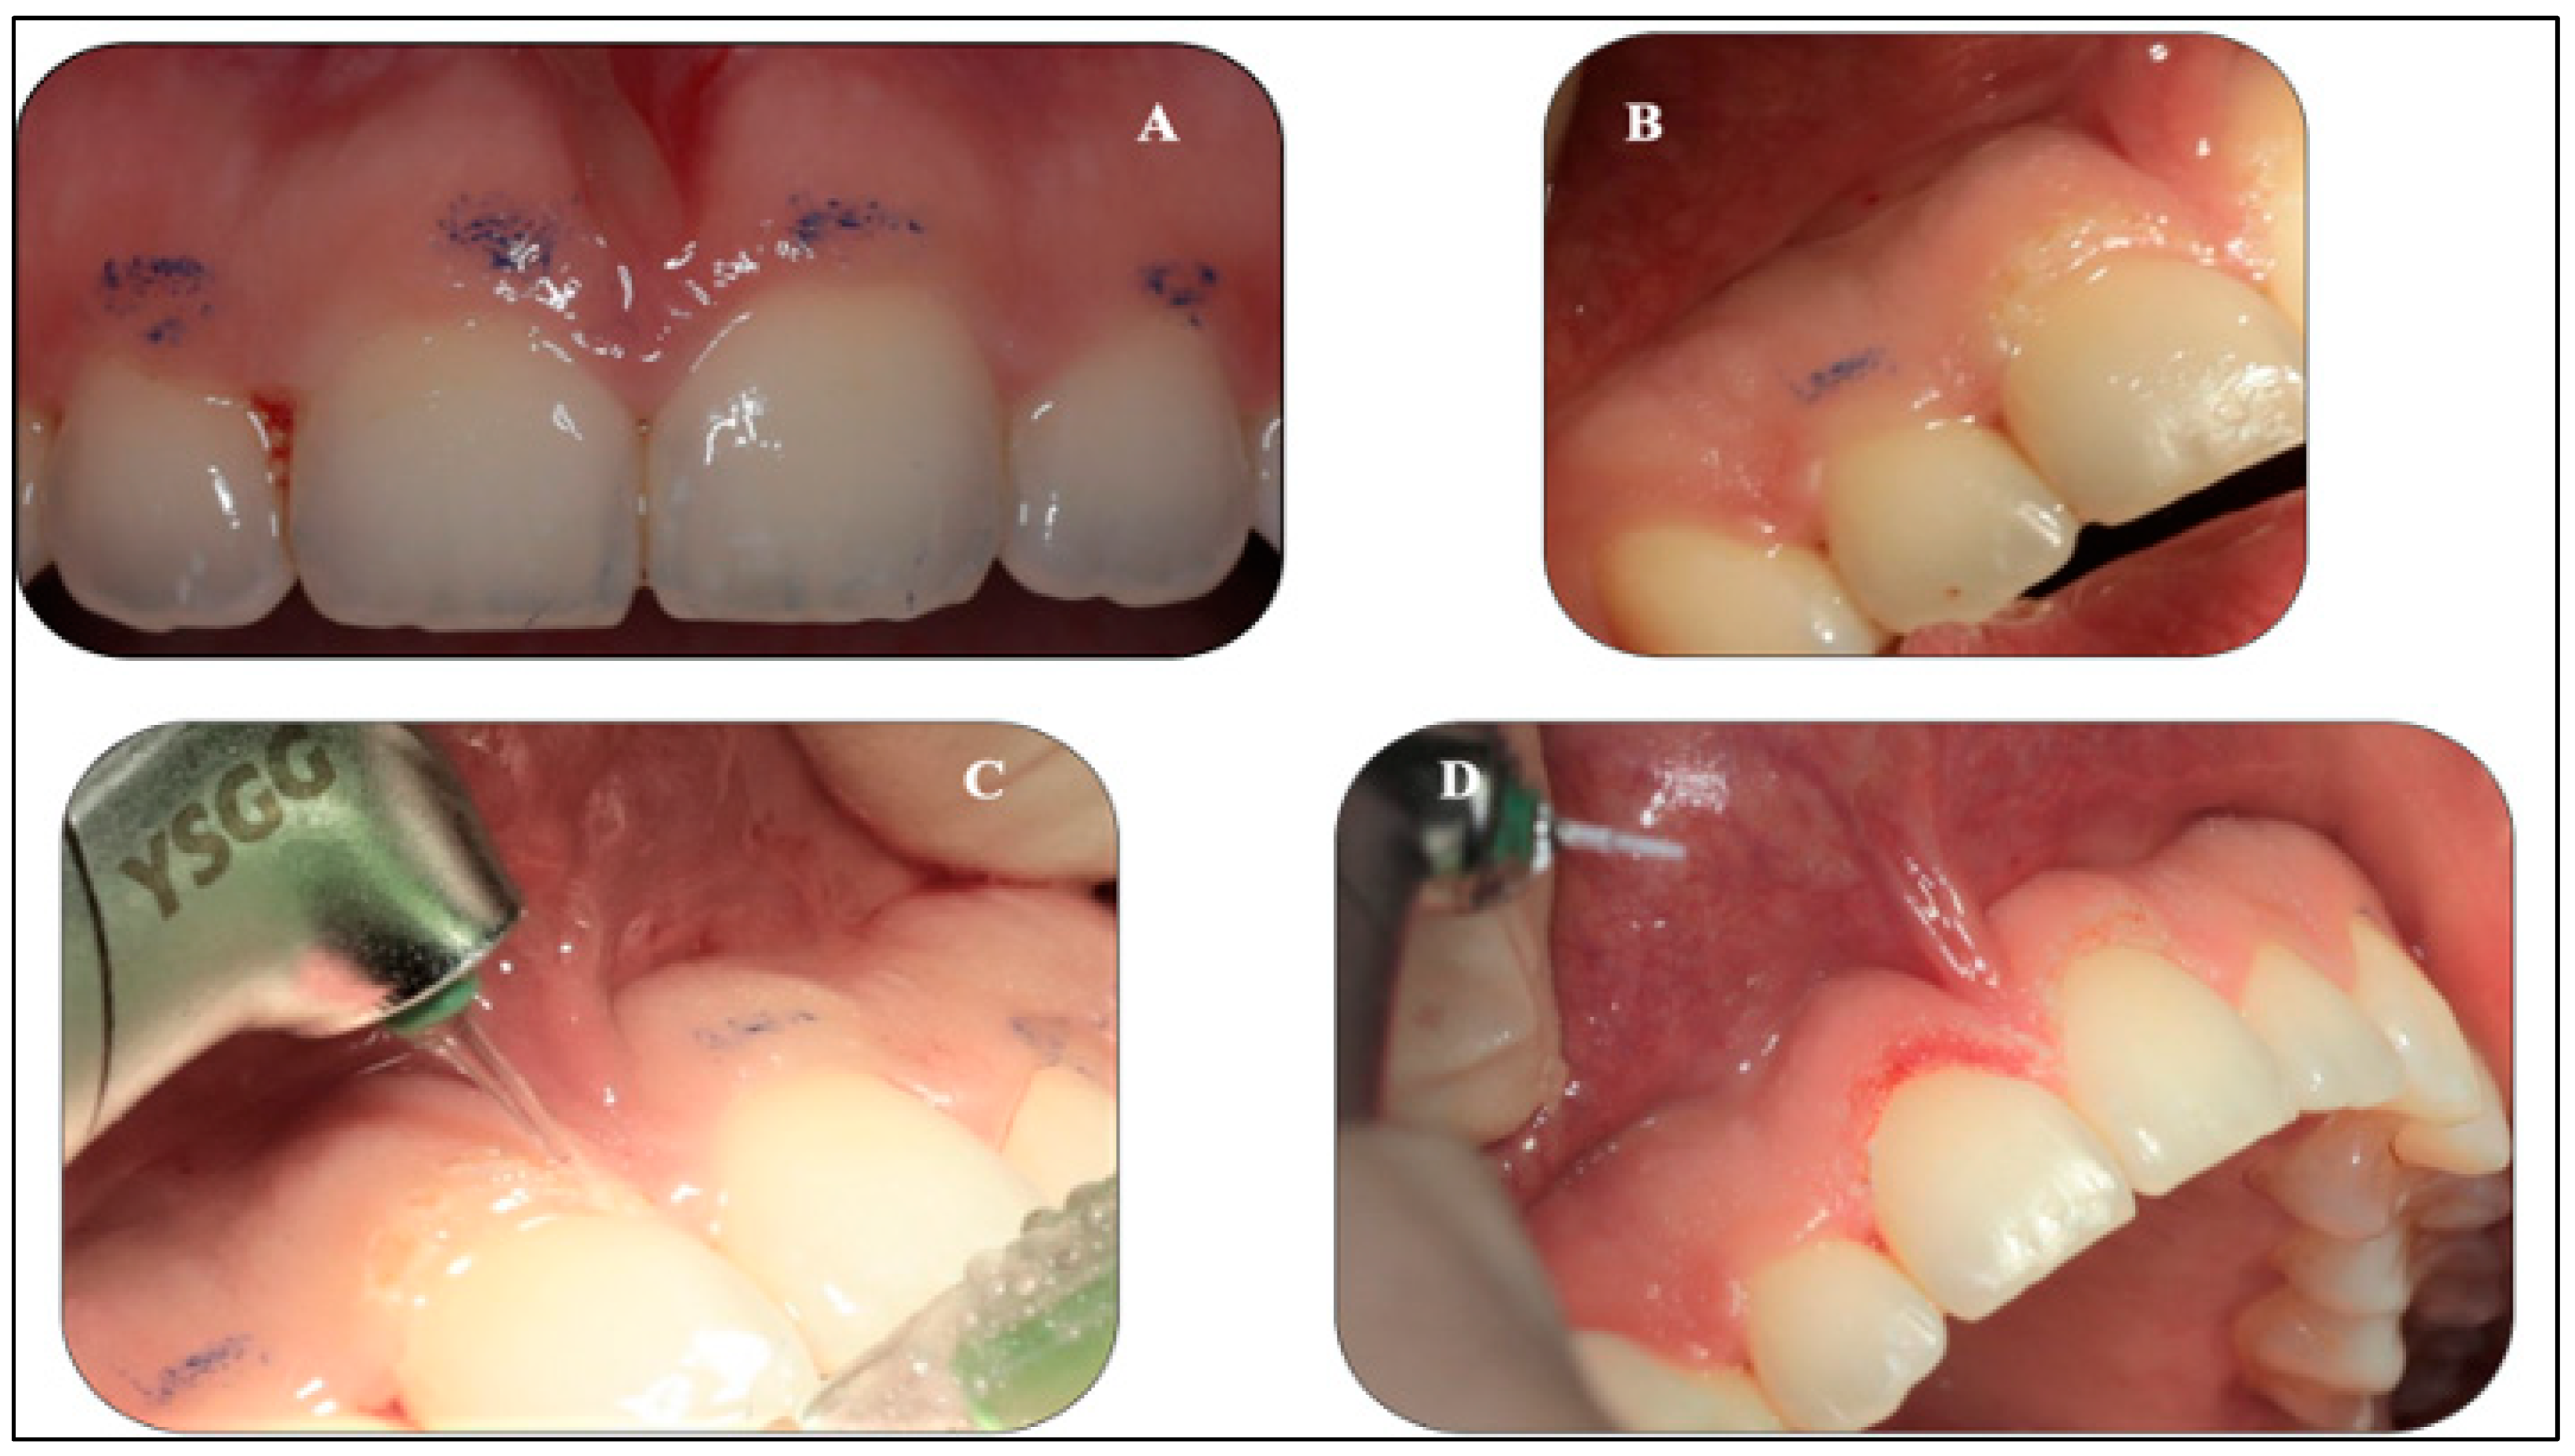

2.5.1. Gingivoplasty Procedure

2.5.2. Upper Midline Frenectomy Procedure